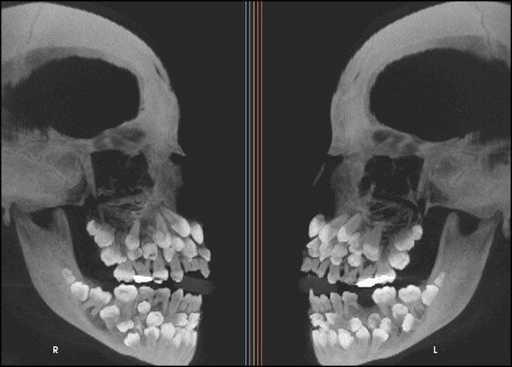

4. 多牙症患者的X光。

一些奇怪的X光照片,看完整个人都不好了……-4.jpg